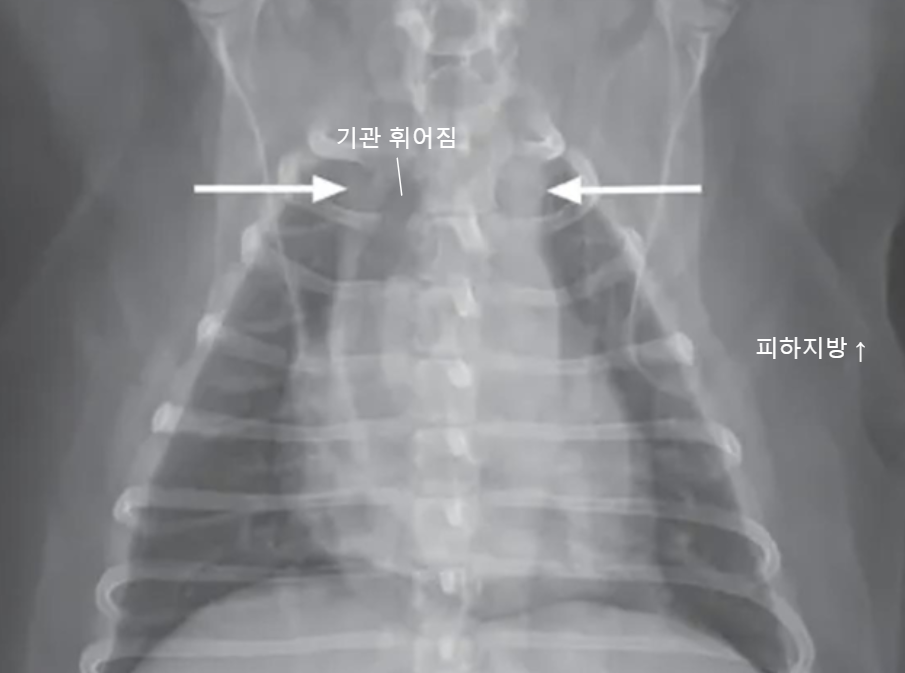

![]() | - 종격동이 2배 이상 커지고, 기관이 휘어졌는데.. - 종양 때문일 수도 있지만, - 이건 살이 너무 많이 쪄서.. |